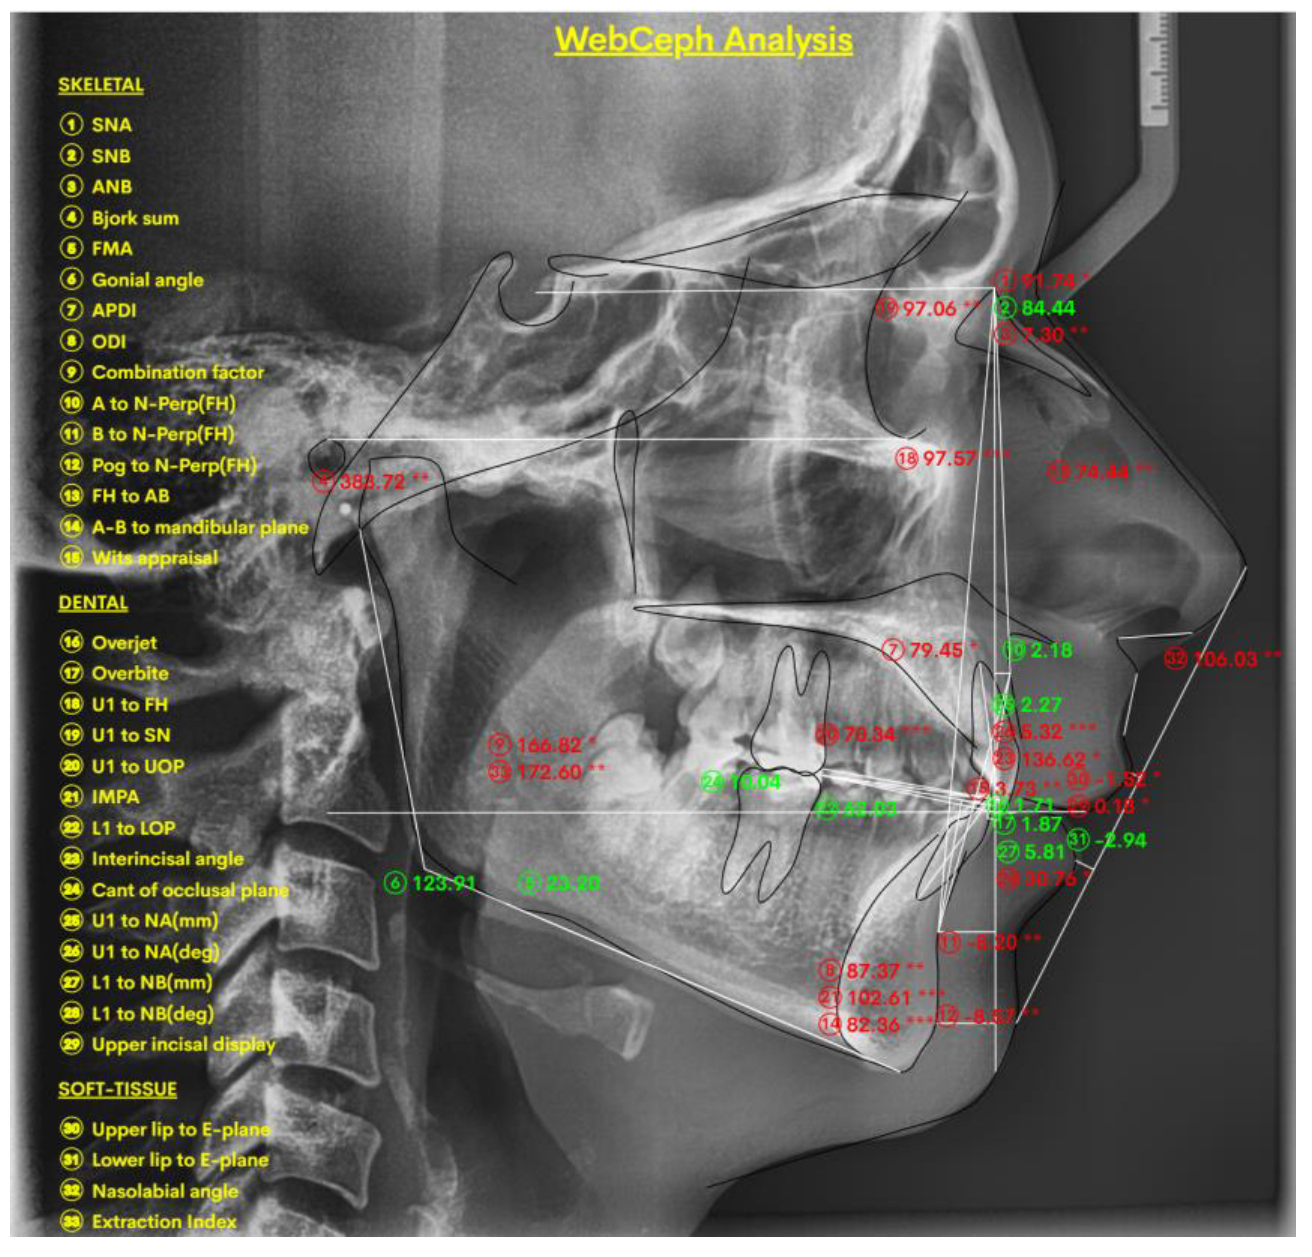

2.1.1. Digital Lateral Cephalometric Measurements and Protocol

- Mahto, R.K.; Kafle, D.; Giri, A.; Luintel, S.; Karki, A. Evaluation of Fully Automated Cephalometric Measurements Obtained from Web-Based Artificial Intelligence Driven Platform. BMC Oral Health 2022, 22, 132. [Google Scholar] [CrossRef]

- Yassir, Y.A.; Salman, A.R.; Nabbat, S.A. The Accuracy and Reliability of WebCeph for Cephalometric Analysis. J. Taibah Univ. Med. Sci. 2022, 17, 57–66. [Google Scholar] [CrossRef]

- Katyal, D.; Balakrishnan, N. Evaluation of the Accuracy and Reliability of WebCeph–An Artificial Intelligence-Based Online Software. APOS Trends Orthod. 2022, 12, 271–276. [Google Scholar] [CrossRef]

- Natrajan, K.; Selvarajan, K.; Geevee, A.; Elango, E.; Sankar, H.; Krishnan, P. Accuracy and Reliability of WebCeph on Posteroanterior Cephalogram—A Retrospective Study. J. Contemp. Orthod. 2024, 8, 491–495. [Google Scholar]